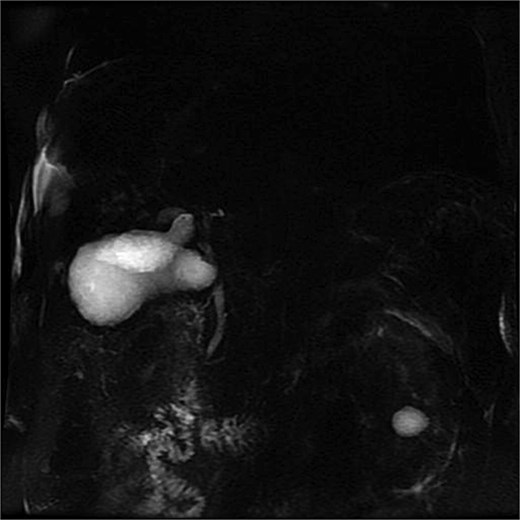

Lab tests showed leukocytosis (15.2 × 103/μl), thrombocytopenia (95.8 × 103/μl), elevated CRP (25.22 mg/dl), procalcitonin (4.49 ng/ml), and total bilirubin (3.5 mg/dl). Liver function was otherwise normal. Ultrasound revealed lithiasic cholecystitis with hydrocholecystosis. Computed tomography (CT) failed to detect duplication (Fig. 1a and b). MRCP confirmed H-type duplicated gallbladder with two independent cystic ducts and mild extrinsic compression of the extrahepatic bile duct (Mirizzi-like pattern) (Figs 2 and 3). MRI sequences (T1 LAVA-Flex and T2 PROPELLER with fat suppression) also demonstrated the duplicated gallbladder and supported the MRCP findings (Fig. 4). No choledocholithiasis was seen.

MRCP showing duplicated gallbladder (H-type), with two independent cystic ducts draining into the common bile duct.

MRCP (thick-slab 2D coronal oblique) showing duplicated gallbladder (H-type) with two independent cystic ducts and no evidence of choledocholithiasis.

3D T2-weighted MRCP with maximum intensity projection (MIP), showing duplicated gallbladder (H-type) and biliary anatomy.

Most cases are diagnosed incidentally, but preoperative identification via MRCP is crucial in complex or recurrent biliary disease [8] (Figs 2–5). Anatomical variants increase the risk of bile duct injury, bleeding, or incomplete surgery [9]. Surgically, duplicated gallbladders pose technical challenges, especially when inflamed or fibrotic. Higher conversion and complication rates have been reported [7, 11].